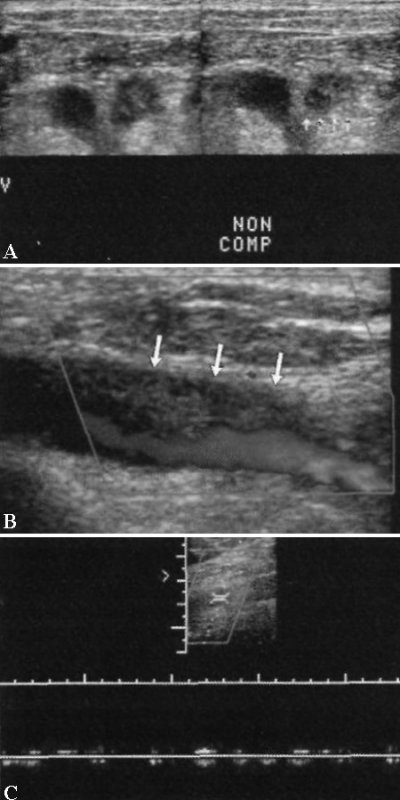

Наиболее специфичным ультразвуковым признаком тромбоза глубоких вен верхних конечностей является утрата полной сжимаемости сосуда. Следующим по специфичности методом УЗИ ТГВ является цветовая допплерография. Быстрый вдох обычно вызывает спадение внутренней яремной и подключичной вен. Отсутствие этого признака, нарушение подвижности стенки сосуда или отсутствие изменения скорости кровотока могут быть признаками наличия обструктивного тромба. Пульсовая допплерография позволяет обнаружить нарушения кровотока, характеризующееся уменьшением сердечной пульсации и дыхательной периодичности, а также выявить отсутствие кровотока (фото 10, фото 11).

Фото 11. Тромбоз глубоких вен верхних конечностей. А – поперечное ультразвуковое изображение: стрелками отмечен эхогенный тромб. В – допплерограмма: сосуд невозможно сдавить, наблюдается неполное заполнение цветом и патологическая кривая потока. Также на цветовой допплерограмме отмечается частичное заполнение венозного просвета из-за наличия краевого тромба (отмечен стрелками). С – спектральная допплерограмма области полной окклюзии свидетельствует об отсутствии кровотока; наблюдаются только движения, опосредованные прилегающей артерией